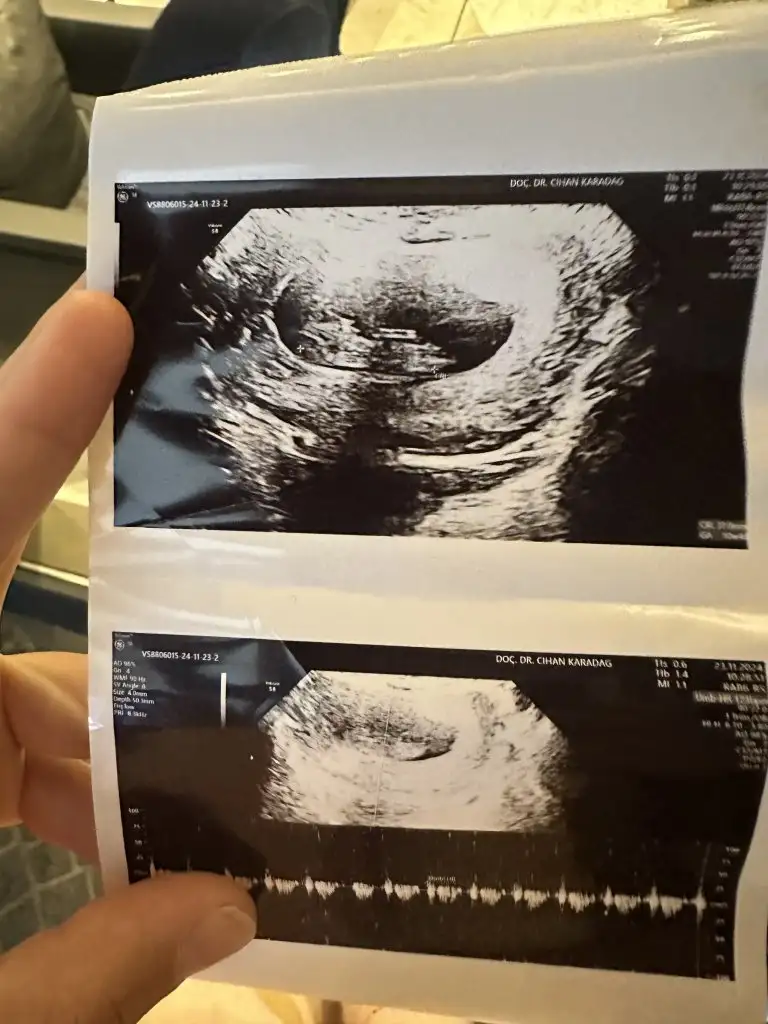

Sana bu mesajı yazdıktan bi kaç saat sonra baya kahverengi akıntım oldu yatayım dinleneyim dedim geçer ama pembe kırmızıya döndü hemen acile gittim. Bebekte kesede bi sorun yoktu çok şükür kalp atışı vs herşey normaldi. Progestan başladım ve dinlenmeye çalışıyorum. Doktor sebebini söylemiş miydi ? Senin de 8. Haftalardı sanırım yanlış hatırlamıyorsam.Bence çok vakit kaybetmeden acile git bir şekilde müdahale edilir ya da varsa bi sorun tespit edilir. En azından için rahat eder.

haftaya doktor randevum benimde . Tam 12. Hafta olcak. Ense kalınlığı vs ölçülecek fetal dna içinde gün alacağım. Geç kalmıyorumdur herhalde